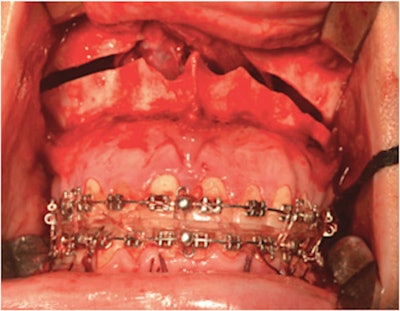

The healthy patient, who had a skeletal class III deformity, underwent jaw surgery with a LeFort I osteotomy with horizontal maxillary advancement, mandible retraction, and clockwise rotation through sagittal osteotomies. In addition, she underwent a surgical procedure to reshape her chin, according to the report.